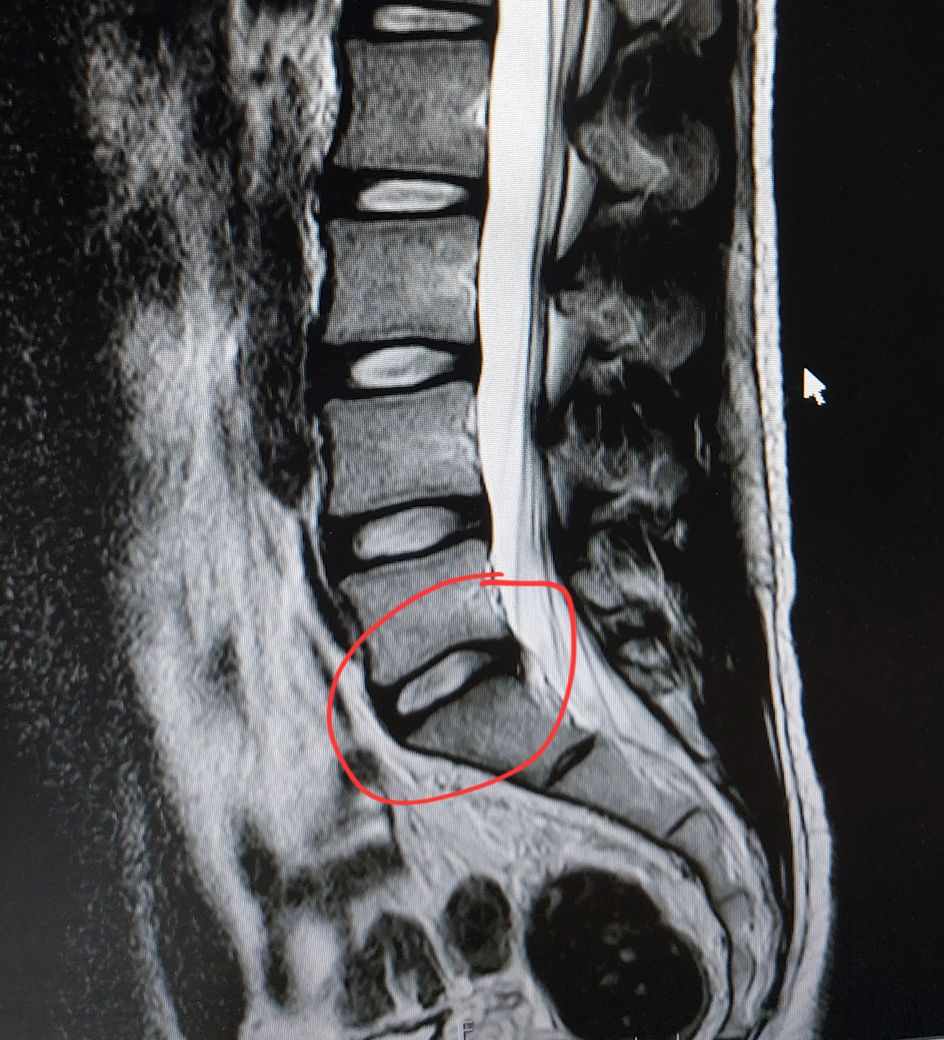

사진은 제 mri입니다